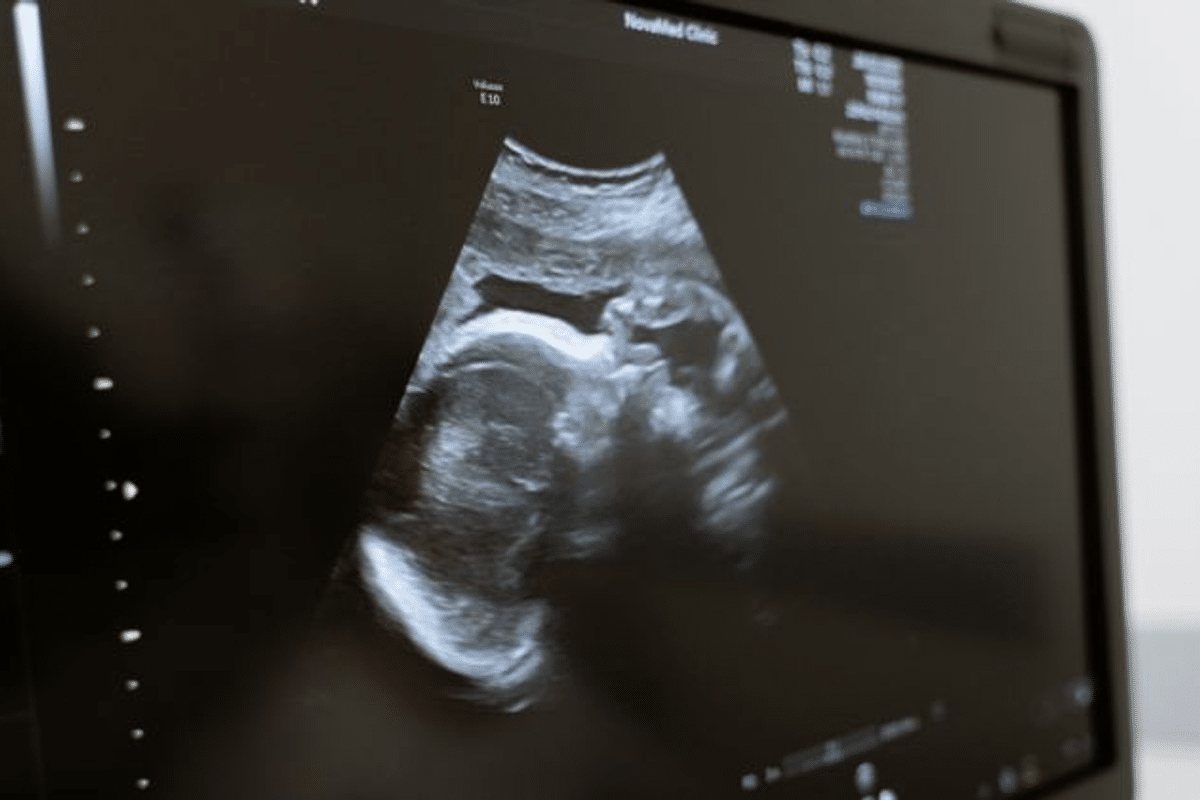

Ibu-ibu mesti tertanya kenapa bayi dalam perut selalu menendang.

Ini 3 sebab utama kenapa bayi banyak menendang seperti dikongsi Klinik Nuha Bangi:

Nak suruh ibu jauhkan daripada cahaya, dia silau.

Nak suruh ibu berbaring mengiring ke kiri sebab peredaran darah akan lebih baik.

Ibu makan makanan yang manis dan pedas.

@kliniknuhabangi Ibu-ibu mesti tertanya kenapa baby dalam perut selalu menendang kan ?? Tengok sini sebab apa baby suka menendang 🤭 #kliniknuhabangi💜 #viralvideo #fypシ゚viral #pregnant🤰 #antenatal #ultrasound #5dscanbaby #fyppppppppppppppppppppppppp